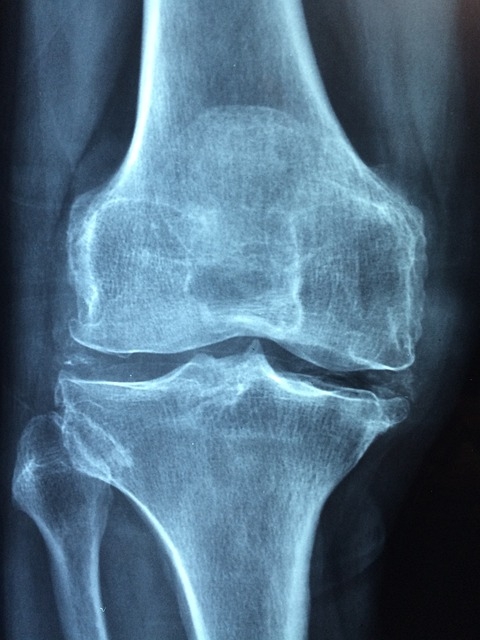

Est-ce que le CBD est bon pour l’arthrose ?

Les recherches scientifiques actuelles tentent de montrer que les propriétés analgésiques et anti-inflammatoires du CBD peuvent soulager la douleur associée à l’arthrose en imitant la réponse des récepteurs endocannabinoïdes sans provoquer d’effets secondaires.

Les recherches scientifiques actuelles tentent de montrer que les propriétés analgésiques et anti-inflammatoires du CBD pourraient soulager la douleur associée à l’arthrose en imitant la réponse des récepteurs endocannabinoïdes sans provoquer d’effets secondaires.

Citrus CBD Oil – 5-30% – Hemp Drop Des études ont également été menées pour montrer que l’huile de CBD peut être un traitement sûr et efficace contre les douleurs articulaires causées par l’arthrose.